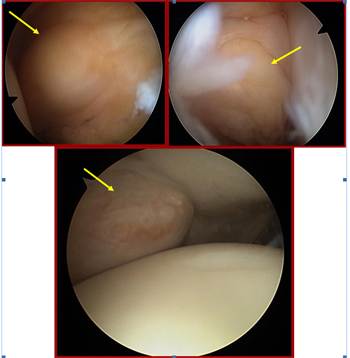

Se remite la pieza quirúrgica para estudio anatomopatológico (ver imagen 4), siendo informada la muestra como “tumoración de células gigantes”.

Imagen 4: Tumor de células gigantes (pieza quirúrgica).